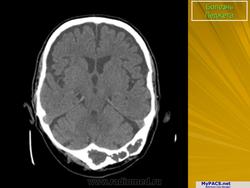

Педжета болезнь (J. Paget англ. хирург, 1814-1899; синоним: деформирующий остоз, деформирующий остит, деформирующая остеодистрофия) - заболевание скелета, при котором наблюдается поражение одной или нескольких костей в результате патологической перестройки костной ткани.

Принято различать три фазы развития П. б.: очаговая интенсивная резорбция кости (остеолитическая, или деструктивная, фаза), смешанная фаза, когда наряду с рассасыванием кости идут процессы новообразования ее, и остеобластическая, или склеротическая, фаза с образованием типичных мозаичных структур.